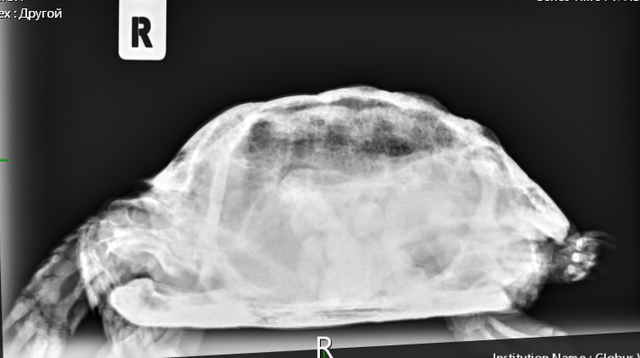

Консультанты moth Ваше имя: Мария Локация: Москва Опубликовано: 7 сентября 2023 Консультанты Опубликовано: 7 сентября 2023 @Алёна.Е. Вам всё в ту же клинику с ней нужно - делать рентген лапы и смотреть что с костями. Если там внутри всё сгнило, то только ампутация. Если нет, то можно пробовать антибиотики. Вы ещё не записывались на приём? Рыбу она поела?

Консультанты moth Ваше имя: Мария Локация: Москва Опубликовано: 8 сентября 2023 Консультанты Опубликовано: 8 сентября 2023 @Алёна.Е. врач ответила, что нужно обязательно рентген. Мускусные черепахи склонны к "гниению" конечностей и скорее всего там гнойный артрит и некроз + сверху бактериальный дерматит. рыбу конечно предлагайте.

Алёна.Е. Ваше имя: Алёна Локация: Пермь Опубликовано: 13 сентября 2023 Автор Опубликовано: 13 сентября 2023 Здравствуйте, были на приёме в клинике 11.09. Рентген сделали, назначили антибиотик, ванны с бетадином и прослушивание. От рыбы также отказывается. Если поможет то лапку попробуем спасти. Фаланги уже рыхлые до локтя. Есть вероятность опухоли, но гисталогию не делали ещё.

Консультанты moth Ваше имя: Мария Локация: Москва Опубликовано: 13 сентября 2023 Консультанты Опубликовано: 13 сентября 2023 @Алёна.Е. а снимков нет на руках? я бы нашему врачу показала, спросить её мнение. Попробуйте предложить улиток, мидий или креветку (желательно сырую) без панциря